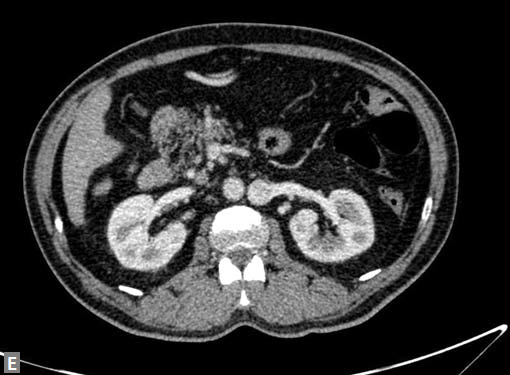

The most common mass lesion in heart is thrombus. Postinfarct clot is common in LV apex. Postinfarct aneurysm of LV may have clot. Rheumatic mitral valve disease with AF has left atrial (LA) appendage thrombus. Large one can extend to body of thrombus. Patients with arrhythmogenic right ventricular dysplasia (ARVD), sarcoidosis can have thrombus in right ventricle. SVC and IVC thrombus can extend to right atrium. Long-standing catheters can be source of thrombus in innominate veins and SVC.

Carcinomas of liver, kidney can directly extend to IVC and then into RA.

Thrombosis is associated with lower limb veins thrombosis. Occasionally renal vein thrombosis can extend to IVC. In Budd-Chiari syndrome, chronic stenosis of IVC and membrane in IVC are seen.

Along with IVC, relationship of iliac veins and artery is assessed. May-Thurner syndrome occurs when left common iliac vein is compressed between the right common iliac artery and the vertebral body. Reverse May-Thurner syndrome occurs in situs inversus abdominus associated with heterotaxy syndromes.

Leiomyosarcoma is a rare primary tumor which can arise from IVC. Renal cell carcinoma and hepatocellular carcinoma may extend to IVC and reach even RA in contiguity.